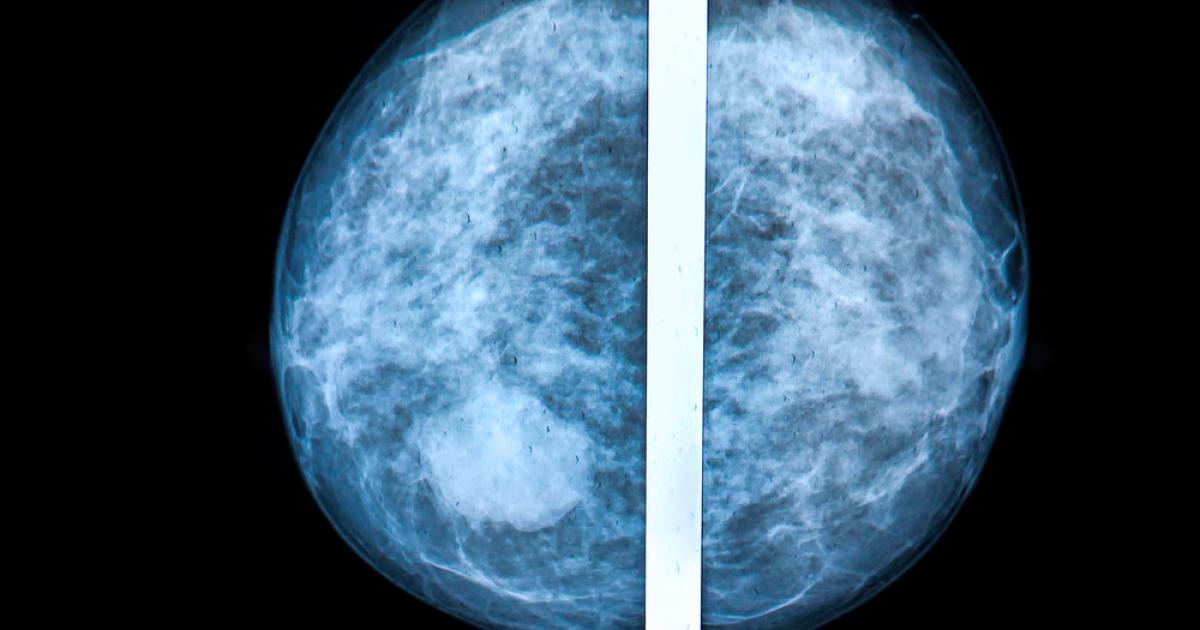

Physicians should be responsible for making sure women with dense breasts understand what the findings mean. In the study — from the University of Virginia School of Medicine — researchers found that the strongest factors in knowing about breast density was whether a physician informed a woman about the density of her breasts, and what alternative screening tools should be used to determine whether or not there are abnormalities in the tissue. The sonogram, for instance, can see things under the skin which can't be felt or are unclear in a mammogram. An MRI (magnetic resonance imaging) of the breast and/or ultrasound are also techniques that can be utilized when necessary.

"However, dense breasts are too frequently not communicated to the patient, or reported in a manner that leaves the patient confused and, therefore, not able to seek further treatment appropriately. The breast cancer field is ineffective in its current state when it comes to early detection of breast cancer in women with dense breasts, putting them at a higher risk for breast cancer," LeMieux says.